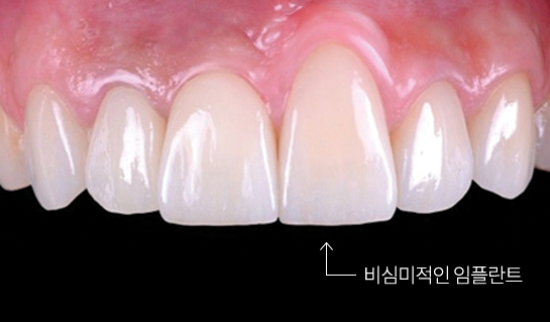

- 금속 노출

치주 조직인 잇몸과 잇몸 뼈에 대한 미흡한 진단으로 무리하게 임플란트를 식립했을 경우 잇몸 들림으로 인해 금속 노출이 되어 심미성이 떨어지는 결과로 이어질 수 있습니다.

치주조직손상 원인

임플란트 보철 부작용이나 수술 부작용의 경우 환자의 부주의가 큰 원인으로 꼽히지만, 치주 조직 손상의 원인은 치주 조직 재생을 소홀히 한 의료진의 원인이 크다고 할 수 있겠습니다. 치아 발치 후 36개월 내에 34mm 정도의 잇몸과 잇몸 뼈의 퇴축이 발생하는데요, 치주 조직 손상으로 인한 부작용인 임플란트 탈락, 잇몸 들림, 금속 노출 등의 위험을 줄이려면 발치 후 치주 조직 재생을 극대화해야만 합니다.

강남새로치과에서는

임플란트 식립을 동반한 외측동저 거상 시 연어주사가 상처재생을 촉진시킨다는 논문 자료를 기초로 연어주사 임플란트를 최초 시행한 정재욱 대표원장만의 타 병원 대비 월등한 실력으로 치조제보존술을 시행하여 치주 조직인 잇몸과 잇몸 뼈의 유지 및 복원 효과를 최대한으로 끌어올립니다.